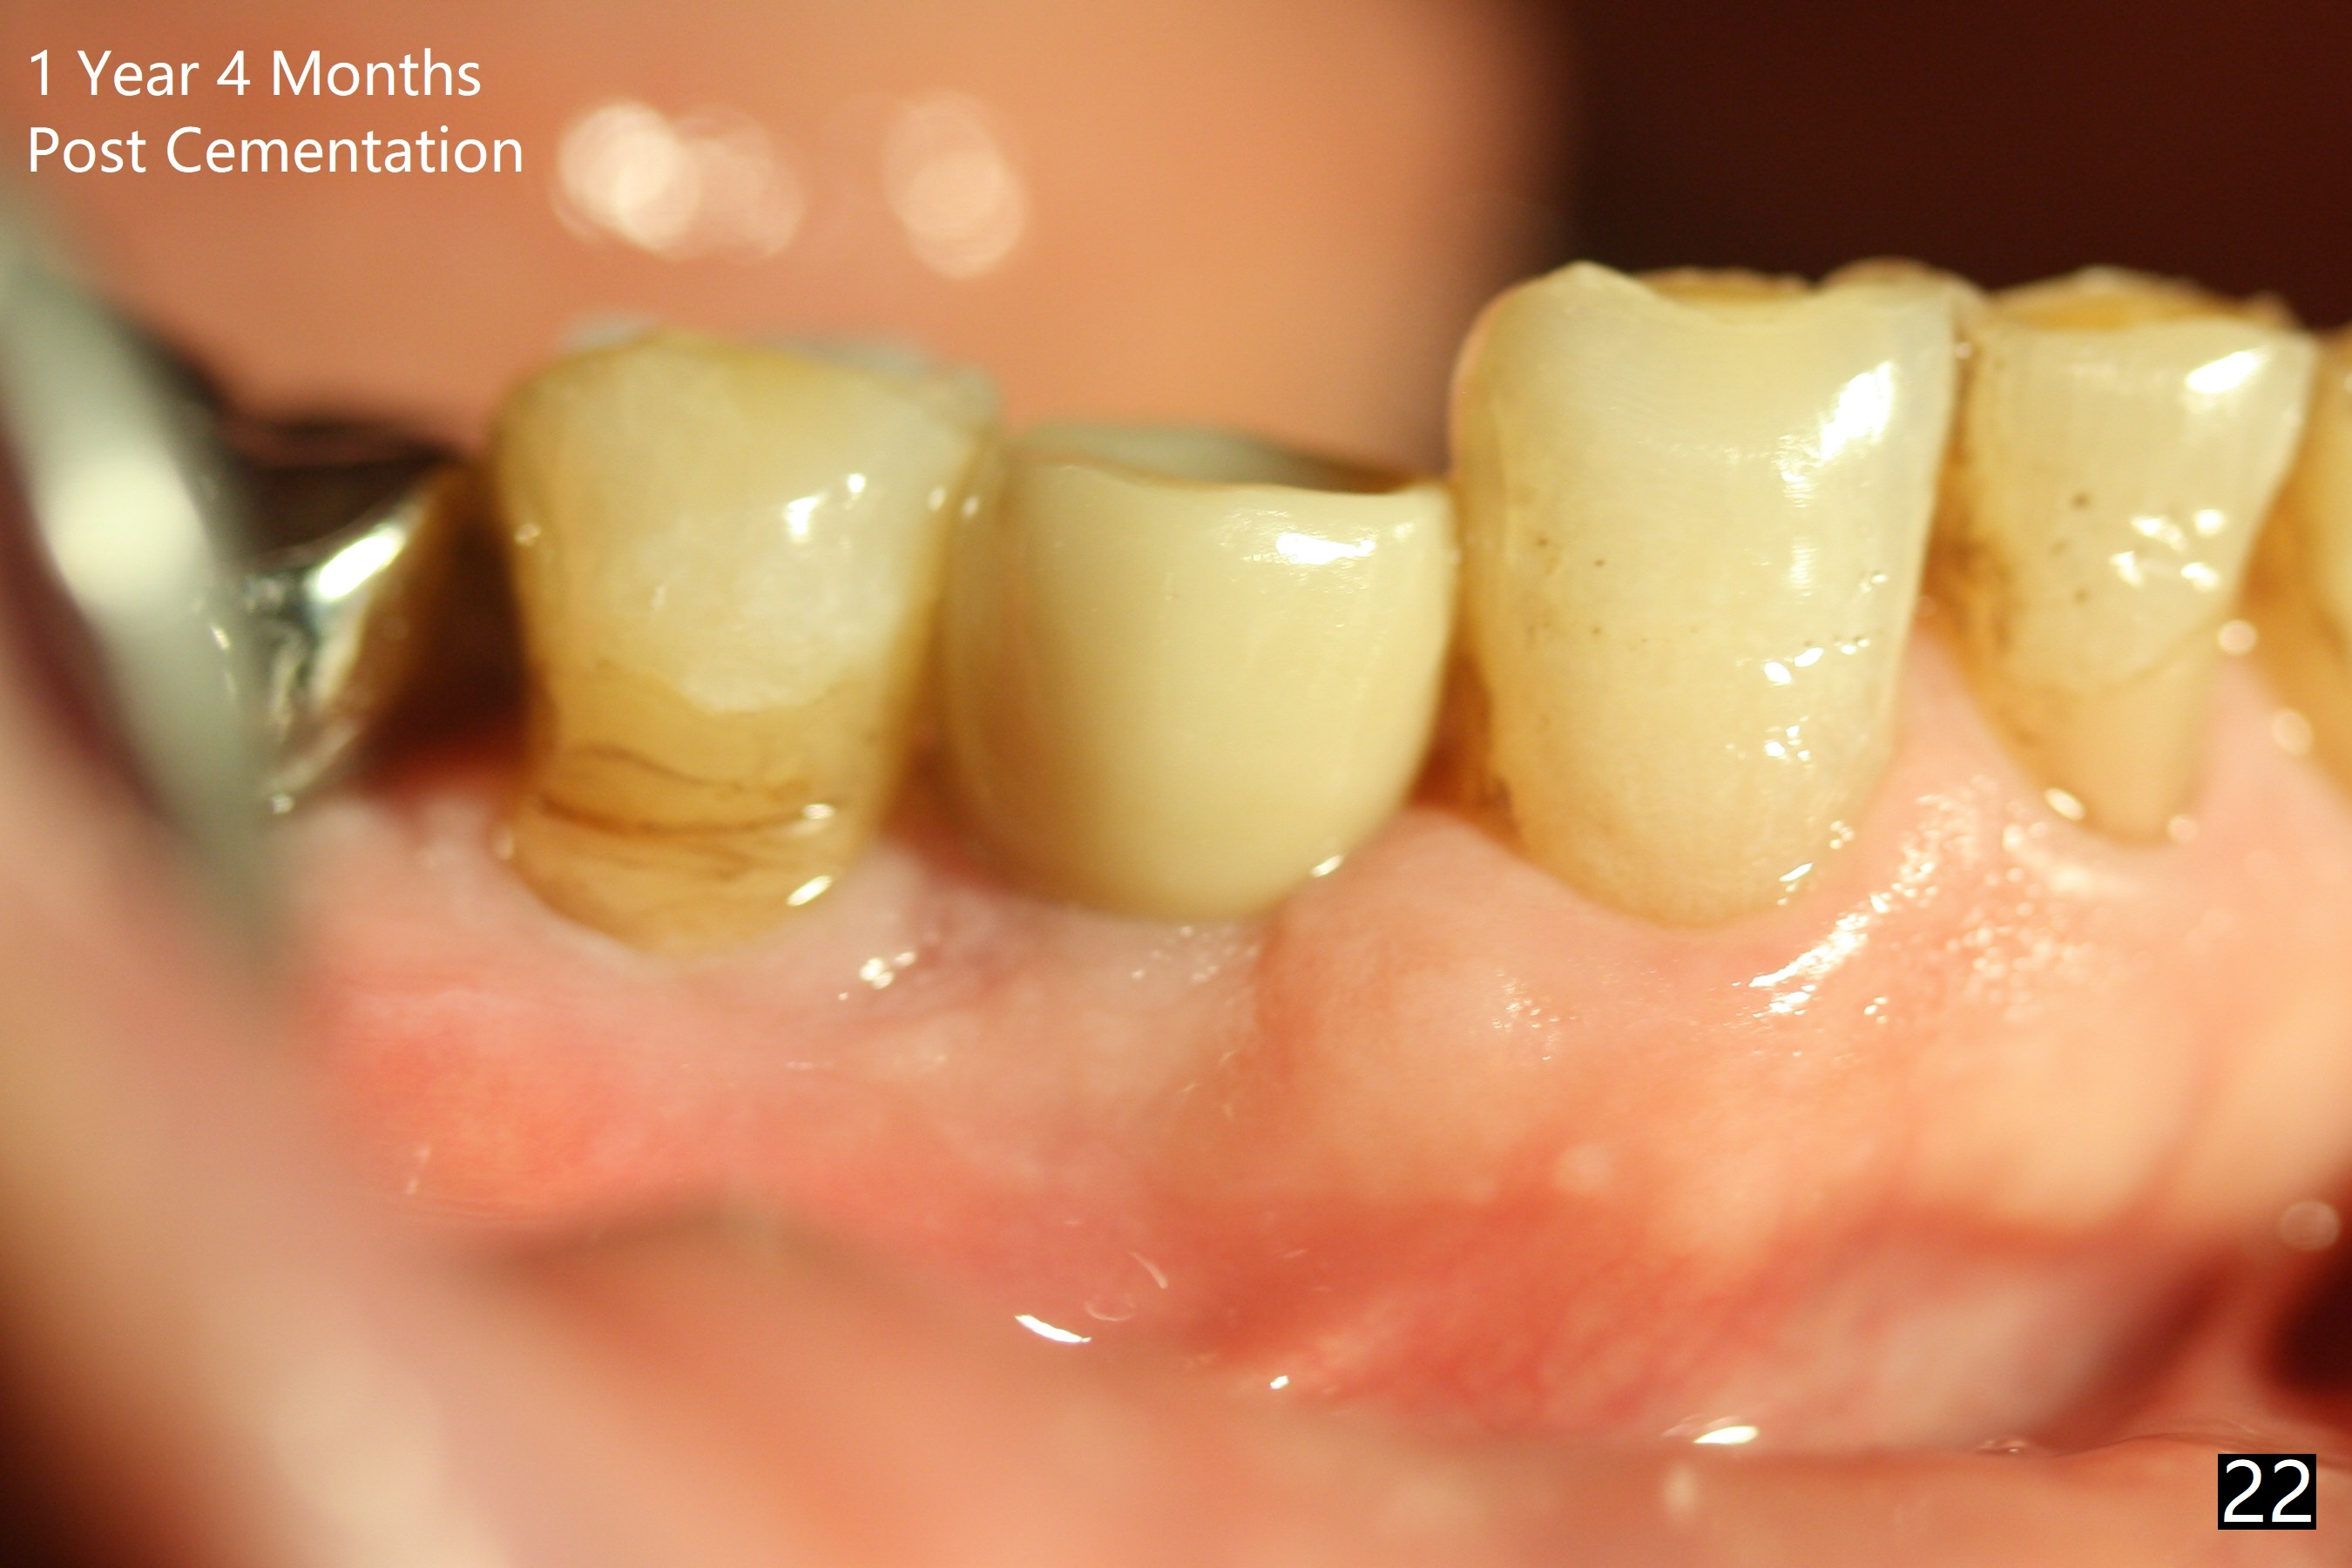

The right posterior final restorations (Fig.14) are fabricated as planned: increase in vertical height (Fig.15). The increase is minimal (Fig.14, 17(#2 limited crown height), 16 (#2 crown being thin *)). Fig.17,18 are taken immediately post cementation. There is no bone loss 10 months post cementation (Fig.19,20). The gingiva is healthy around the implant crowns (#2, 4 and 28) 1 year 4 months post cementation (Fig.21,22).